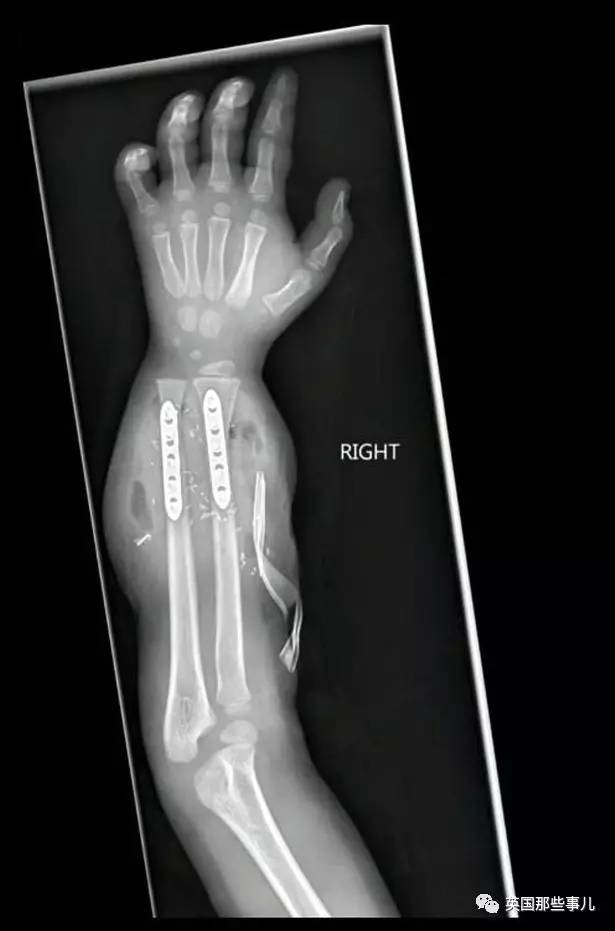

Zion在费城儿童医院进行了一项非常前沿,风险也很大的手术:

双手移植。

手术进行了整整11个小时,

40名医生、护士聚集在手术室里,

“手术成功了。”

接下来,就是适应问题。

手术后才几天,Zion就能够通过自己手臂上的韧带,

轻轻地动动手指。

由此,漫长的康复训练也就开始了。

手术后6个月,Zion已经可以用新的双手握笔、笨拙地吃饭。

8个月,他就能够使用剪刀和蜡笔;

手术后一年,他可以双手用劲,高兴地挥舞球拍。

如今,他已经能够自己吃饭、写字、穿衣服,

甚至还能用手抛足球,玩棒球。

医生对他的脑部进行扫描,

发现Zion的大脑已经发展出控制这双手的能力,

同时,也能将手上的触觉,传送回大脑。